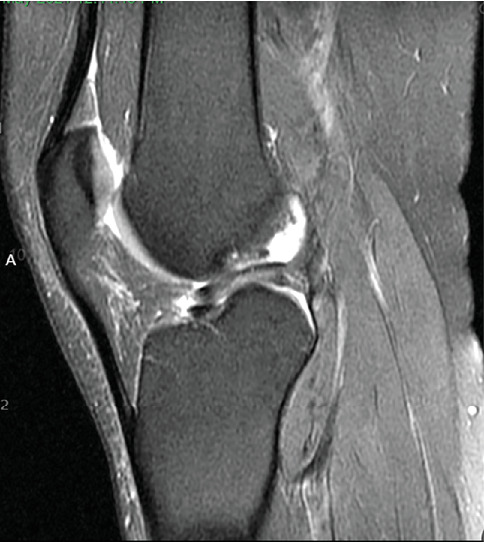

Purpose: Our work describes the use of matrix-induced autologous chondrocyte implantation (MACI) for a lateral tibial plateau osteochondral defect, in the setting of a concomitant meniscus repair and anterior cruciate ligament (ACL) reconstruction. To our knowledge, there is minimal research describing the application of MACI for cartilage defects of the tibial plateau, which brings about its own challenges. Methods: A 26-year-old male presented with lateral right knee pain and instability following a soccer injury. A bucket-handle lateral meniscus tear, 2 cm by 2 cm osteochondral defect of the lateral tibial plateau, and complete ACL tear were identified on magnetic resonance imaging (MRI). Our case vignette describes a two-stage MACI procedure for an osteochondral defect of the lateral tibial plateau with concurrent all-inside meniscus repair and ACL reconstruction using bone-patellar tendon-bone (BTB) autograft. Results: Follow up period was 20 months with excellent patient satisfaction and resolution of pain. Outcome measures (International Knee Documentation Committee (IKDC)) and Knee Injury and Osteoarthritis Outcome Score (KOOS) returned to preinjury levels at 8.5 months. Return to sport was achieved at 10 months postoperatively. Conclusion: The miniopen MACI procedure provides a logistically reasonable technique mitigating the anatomic challenges of tibial plateau osteochondral defects and potentially providing improved long-term outcomes. It is our hope that this work will contribute to the current understanding of the treatment options for osteochondral defects of the tibial plateau.

Abstract Image